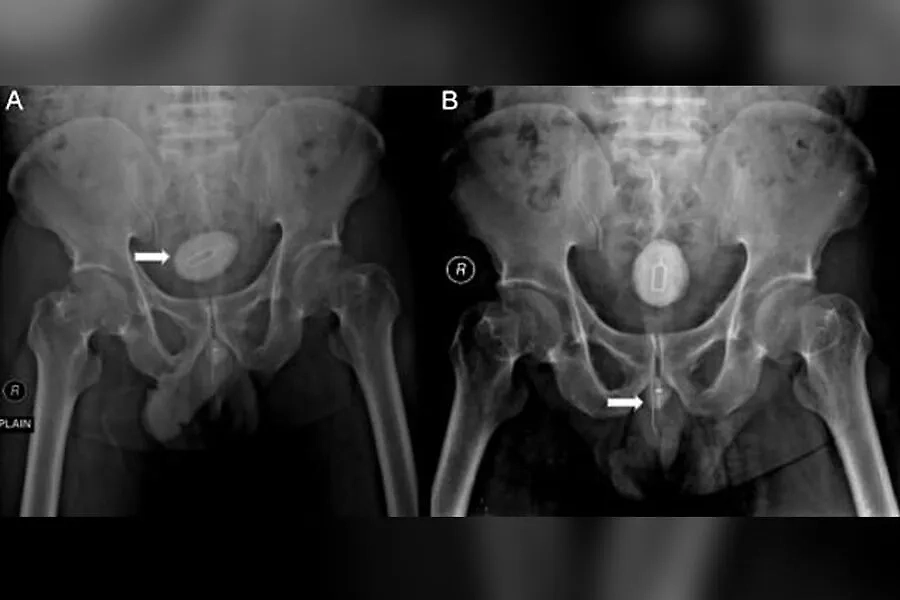

Рентгеновский снимок жителя Индонезии, который ввёл в уретру кабель и инструмент для извлечения сим-карты. Фото © sciencedirect.com

Позже выяснилось, что к образованию камня в мочевом пузыре и сильной боли привёл железный инструмент для извлечения сим-карт. Его, а также электрический кабель длиной 10 сантиметров и восьмисантиметровую иглу, перевязанную резинкой, удалили. Через неделю после процедуры индонезиец уже смог нормально ходить в туалет, а через полтора месяца исчезли последние осложнения, функция почек оказалась нормальной, пишет Daily Mail.